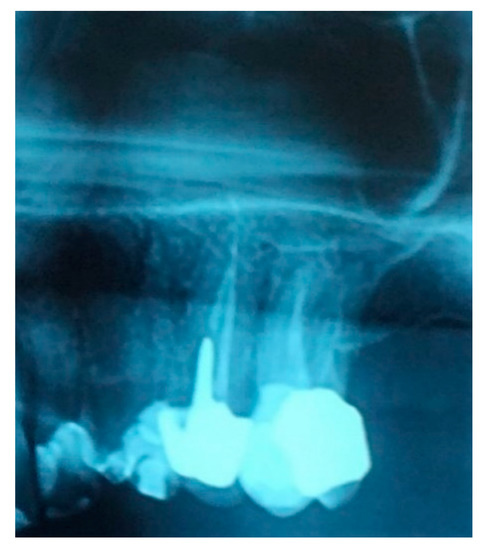

A 52-year-old osteoporotic patient came to our observation. The patient reported the first left maxillary molar painful during chewing. The clinical examination showed tooth and crown mobility and secondary decay under the crown. Radiographic examination showed an osteolytic lesion below the distal root due to an incongruous root canal treatment (Figure 1).

Figure 1.

Detail of the patient’s orthopantomography (OPT) showing the first left upper molar candidate for extraction.